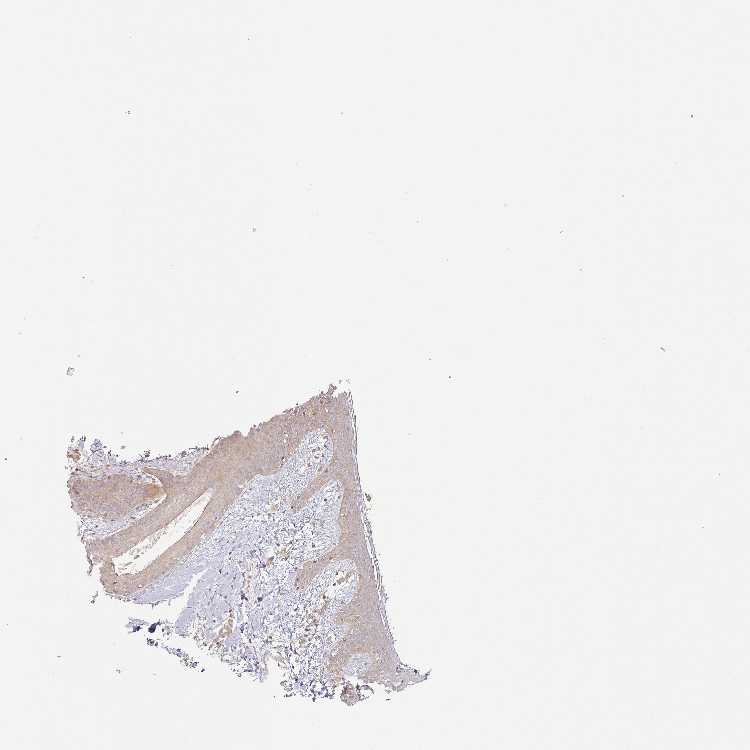

SKIN 1 - Antibody stainingi

Antibody staining in the annotated cell types in the current human tissue is reported as not detected, low, medium, or high, based on conventional immunohistochemistry profiling in selected tissues. This score is based on the combination of the staining intensity and fraction of stained cells.

Each image is clickable and will lead to virtual microscopy that enables deeper exploration of all samples and also displays staining intensity scores, fraction scores and subcellular localization as well as patient and tissue information for each sample.

Antibody HPA048745Antibody CAB009063

Langerhans LowMedium

Fibroblasts MediumMedium

Keratinocytes MediumMedium

Melanocytes MediumMedium

SKIN 2 - Antibody stainingi

Epidermal cells LowMedium